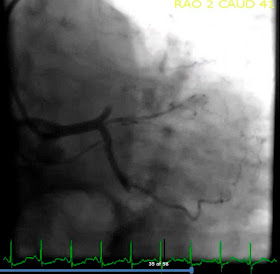

После осмотра кардиолога пациентка была направлена на эхокардиографию. Эхо-окно было плохим, сердце было без структурных нарушений, выпота в перикарде не было. Заподозрив плевральный выпот, врач УЗИ направил пациентку на рентгенографию грудной клетки.

Последующее обследование этой пациентки выявило у нее умеренный туберкулезный выпот слева. Изменения ЭКГ возникли именно в связи с плевральным выпотом. Мы знаем, что заболевания перикарда могут вызвать изменения ЭКГ, имитирующие ОКС. При этом перикардит может привести к элевации сегмента ST. Может ли плеврит без экссудата вызвать изменения ЭКГ? Где проходит реальная граница между плеврой и перикардом?

R-графия грудной клетки.

Последующее обследование этой пациентки выявило у нее умеренный туберкулезный выпот слева. Изменения ЭКГ возникли именно в связи с плевральным выпотом. Мы знаем, что заболевания перикарда могут вызвать изменения ЭКГ, имитирующие ОКС. При этом перикардит может привести к элевации сегмента ST. Может ли плеврит без экссудата вызвать изменения ЭКГ? Где проходит реальная граница между плеврой и перикардом?

Я думаю, что по разным причинам, рентгенография грудной клетки является наименее используемым диагностическим методом в отделении коронарной патологии. Тем не менее, полезность рентгенографии никогда не подвергалась сомнению, а сам метод, в соответствующих условиях, должен использоваться незамедлительно.

Я думаю, что по разным причинам, рентгенография грудной клетки является наименее используемым диагностическим методом в отделении коронарной патологии. Тем не менее, полезность рентгенографии никогда не подвергалась сомнению, а сам метод, в соответствующих условиях, должен использоваться незамедлительно.